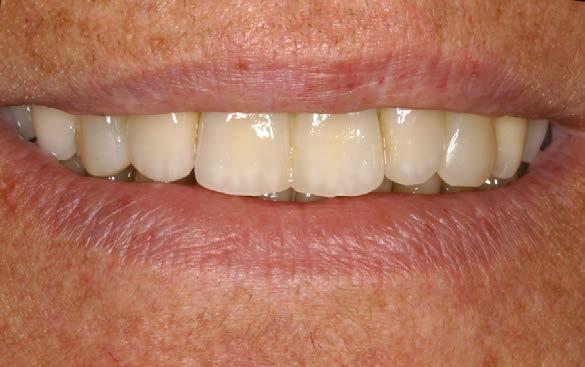

La paciente continúa en seguimiento. A los 8 años, la estabilidad de los tejidos duros y blandos, así como la estética de la rehabilitación, era completa (Figura 9-11). A los 12 años se observó

una buena progresión del tratamiento, sin cambios reseñables (Figura 1214). A los 20 años de seguimiento se constató una evolución estable, sin pérdida ósea en dientes ni implantes, y con buena salud de los tejidos periimplantarios (Figura 15-17).

Figura 7. Colocación de la prótesis

Figura 8. Imagen de sonrisa con la prótesis finalizada.

Figuras 9-10. Imágenes de seguimiento clínico a los 8 años.

Figuras 12-13. Imágenes que muestran el mantenimiento de los tejidos blandos y la estética a los 12 años.